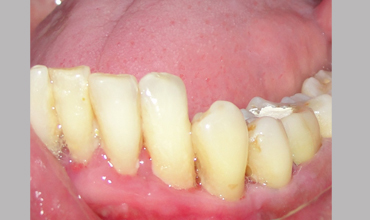

NON SURGICAL MANAGEMENT OF ENDODONTIC LESION AND SURGICAL MANAGEMENT OF PERIODONTIC LESION